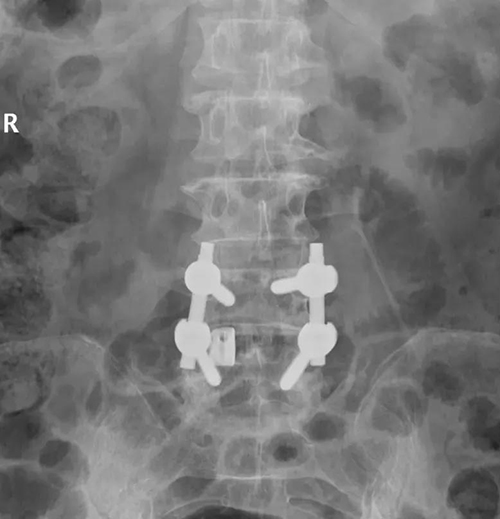

腰椎病例是66岁女性患者,主诉“腰痛10余年,加重5年,双下肢疼痛4年”。查体显示腰椎屈曲活动受限,腰部棘突,椎旁肌无明显压痛,叩击痛。腰椎MRI显示L4/5椎间盘突出并黄韧带肥厚并椎管狭窄。诊断为腰椎管狭窄症,腰椎间盘突出症,高血压病,Ⅱ型糖尿病。

该患者为腰椎间盘突出所致椎管狭窄,L4/5椎间隙退变严重,需要进行腰椎减压椎间融合手术,需要近期的可靠稳定及远期的牢固融合。这种腰椎融合手术一般应用不同规格的PEEK材料椎间融合器,因其椎间融合器上下仅两面植骨及通体无微孔结构,骨接触面积小,术中即刻稳定性及术后远期骨性融合效果往往不佳。丰荣杰主任医师决定为患者采用3D打印钛合金椎间融合器,进行腰椎后路减压植骨融合内固定术。该手术可在融合器前后左右360°以及上下两个面与椎体终板及周围骨质形成全方位无间隙的融合,有效增加骨接触面积,利于自体骨的长入。同时,3D打印钛合金融合器更加接近人体正常骨质的弹性模量,有效避免应力遮挡及骨吸收,与人体骨质有效融合,获得良好的即刻稳定性和远期的牢固骨性融合效果,避免骨性不融合、断钉、断棒等并发症的发生,进一步增加手术效果及手术安全性。

术前X线

术后X线